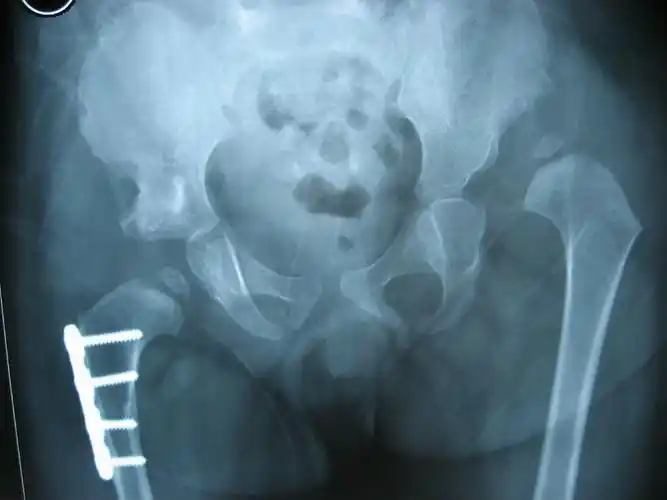

先天髋关节发育不良